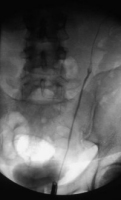

Das Ausscheidungsurogramm ergab eine stumme Niere links (Abbildung 18c). Die retrograde Sondierung zeigte eine deutlische Kompression des Harnleiters sowie eine verkleinerte Niere links mit destruierten Kelchen (Verplumpung) (Abbildung 18d).